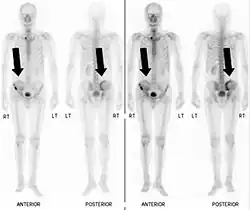

- Vues de fractures pathologiques

Fracture pathologique de l'humérus sur une métastase de carcinome du rein

Fracture pathologique du bras gauche sur une métastase osseuse de cancer du sein

Scintigraphie corps entier avec 99mTc-HDP de la patiente avec une fracture du bras due à une métastase du cancer du sein